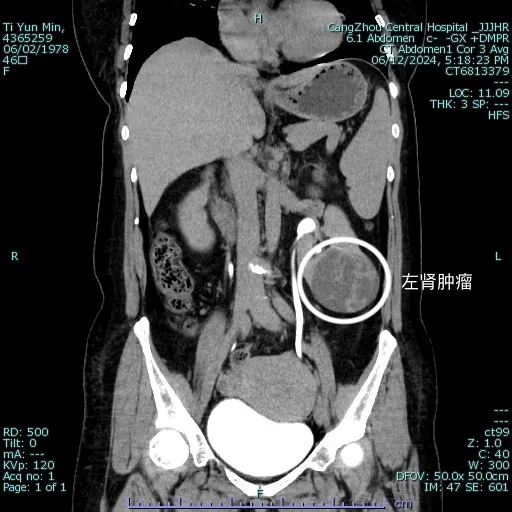

患者提某,女,46歲,主因月經(jīng)量增多伴痛經(jīng)進行性加重10+年入院,入院完善血常規(guī)(血紅蛋白65g/L),婦科超聲提示子宮腺肌癥、多發(fā)肌瘤、縱隔子宮??紤]子宮畸形,常合并泌尿系統(tǒng)畸形可能,完善泌尿系超聲,意外發(fā)現(xiàn)左腎巨大囊實性團塊(大小69x56x58mm)。糾正貧血,同時完善腹部CT提示考慮左腎囊性病變伴出血,泌尿外二科主任劉勝會診考慮左腎囊性腎癌可能性大,可行腹腔鏡腹膜后左腎部分切除?;颊咦訉m腺肌癥,子宮多發(fā)肌瘤,月經(jīng)量大,致中度貧血,左腎腫物考慮腎癌,手術(shù)指征明確,需要行腎臟手術(shù)及婦科手術(shù)。

由于疾病涉及多個科室,經(jīng)過泌尿外科、婦科、麻醉科聯(lián)合充分討論后,為減少患者創(chuàng)傷,解除多重疾患,6月18日行同臺手術(shù),為患者完成左腎部分切除及全子宮切除。術(shù)中,先由泌尿外二科主任劉勝團隊經(jīng)腹膜后行腹腔鏡左腎巨大腫物及腎部分切除,術(shù)中見左腎下極可見一大小約7x6cm腫物,完整切除左腎腫物,最大限度保留患者的腎臟。將腫物置于標本袋中取出,充分體現(xiàn)微創(chuàng)、無瘤原則。后由婦三科(婦科腫瘤外三科)副主任齊冰麗團隊行腹腔鏡全子宮+雙側(cè)輸卵管切除,手術(shù)時間僅50分鐘?;颊咝g(shù)后恢復(fù)好,順利出院。